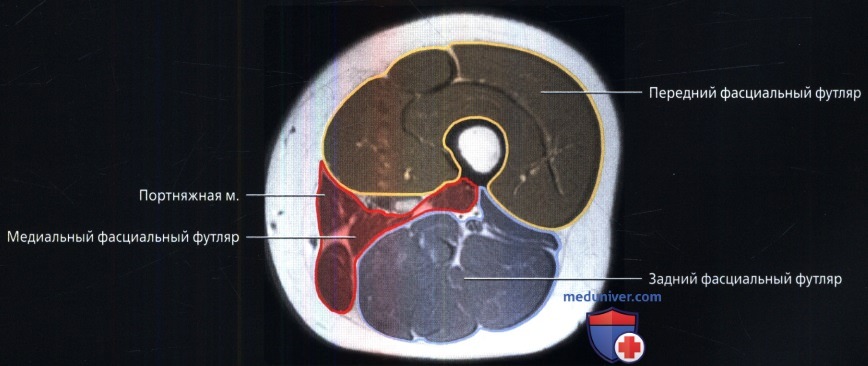

Бедро В Разрезе Фото